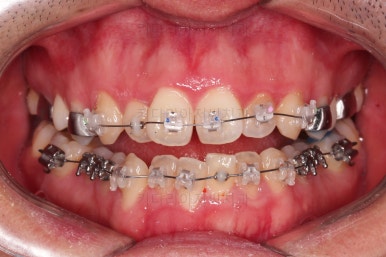

초진 시 입안의 모습입니다.

교합이 많이 안좋습니다.

위아랫니가 서로 엇갈려 가며 지그재그로 껴 들어가야 어금니 맞물림이 생기는데요.

이번 환자분은 아랫니, 아래턱이 전반적으로 앞으로 나와 있어서 교합이 전혀 안되고 있는 상태였습니다.